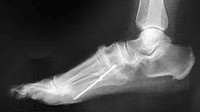

Bila terjadi paralisis (lumpuh) biasanya dimulai dalam beberapa detik sampai lima hari sesudah nyeri kepala. Kelumpuhan anggota gerak yang layuh dan biasanya pada salah satu tungkai.